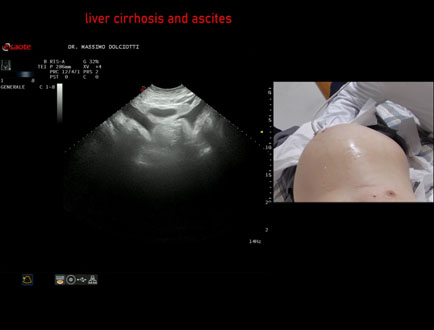

Data inserimento: 26/03/2026

Ecografia del: 17/03/2026

Strumento: Esaote MyLab Eight

Sonda: Convex Multifrequenza 1-8 MHz

Età Paziente: M 60 anni

Motivazione dell'esame: addome globoso, dispnea per piccoli sforzi, potus 1 litro di vino e birra, alvo con feci chiare, nicturia 1 volta.

Commento all'esame: le immagini ed il video documentano il fegato ad ecostruttura spiccatamente disomogenea, a profili irregolari, ridotto di volume e presenza di abbondante ascite.

Conclusioni: cirrosi epatica alcolica scompensata (decompensated alcoholic liver cirrhosis).